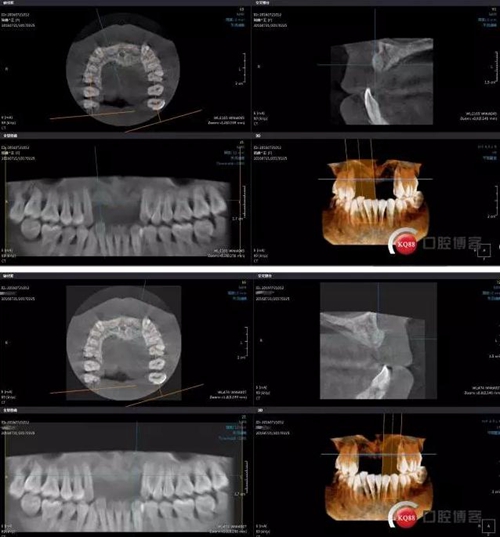

術(shù)后CBCT

靜靜等待3個月全景,未見異常